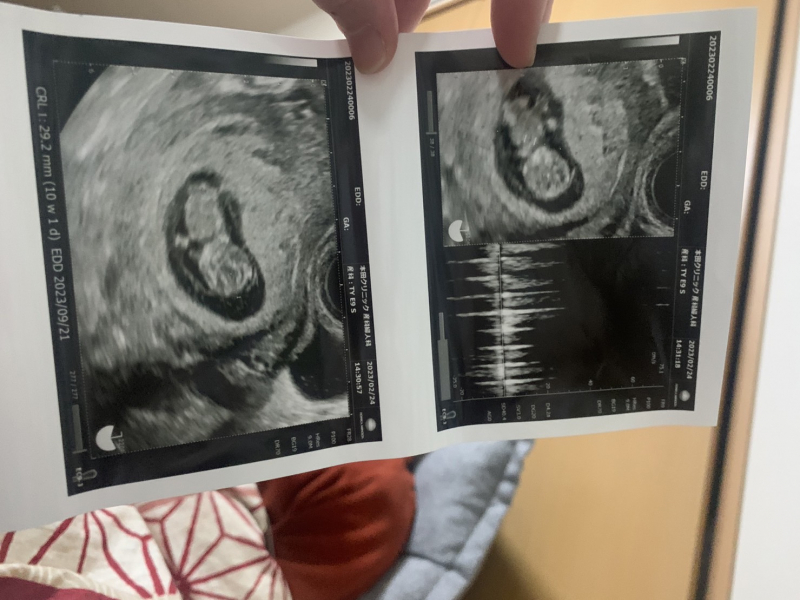

現在29歳、妊娠10週目です

担当の先生からは何も指摘はなかったのですが、ネットで10週目、エコー、ダウン症というワードがでてきて気になって見てみると浮腫があると染色体異常の可能性があるというのを知りました

私のエコー写真にも浮腫があるかどうかの診断をしていただきたいです